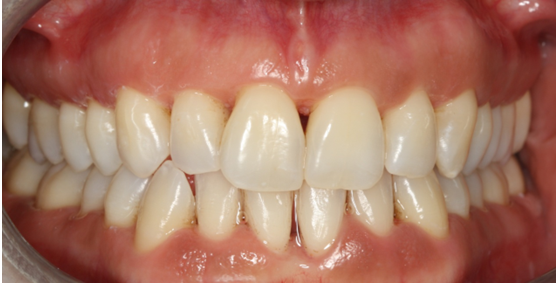

Ασθενής ετών 50 προσήλθε στο ιατρείο με κύρια ενόχληση την αιμορραγία των ούλων και τη μετακίνηση των δοντιών. Οι περιοδοντικοί ιστοί ήταν ρόδινοι και εντοπισμένα ερυθροί, ενώ οι μεσοδόντιες θηλές διογκωμένες. Πολλά δόντια εμφάνιζαν υφιζήσεις, ενώ χαρακτηριστική ήταν η υπερέκφυση και απόκλιση του πλαγίου τομέα άνω αριστερά.

Παράλληλα με την περιοδοντική θεραπεία έγινε η αφαίρεση των παλαιών προσθετικών εργασιών και τοποθέτηση νέων μεταβατικών (προσωρινών) αποκαταστάσεων. Μετά τη μη χειρουργική θεραπεία παρατηρείται απουσία φλεγμονής.

ΑΡΧΙΚΗ ΚΛΙΝΙΚΗ ΕΙΚΟΝΑ

ΤΕΛΙΚΗ ΚΑΤΑΣΤΑΣΗ